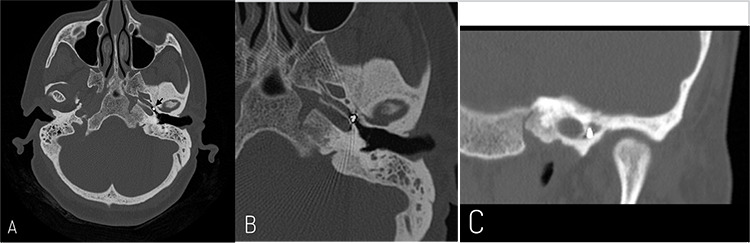

Computed tomography (CT) showed, in left ear, the presence of fluid and mucus in the mastoid air cells and a soft tissue density material occupying partially the middle ear cavity encasing the auditory ossicles without visible stapes. It also reported an incidental metallic foreign body with an intensity of 3,000 HU located at 3.5 mm from the ET opening in the middle ear and measuring 3.2x3.0 mm in size (Figure 2). In the right ear, there was also some fluid and mucus in the mastoid air cells but without any bone changes or associated ossicular chain abnormalities.

Figure 2.

Computed tomography scan, temporal bones. Axial section (A) showing a foreign body in left Eustachian tube (arrow). Magnified axial (B) and coronal (C) sections demonstrating the proximity to the carotid artery